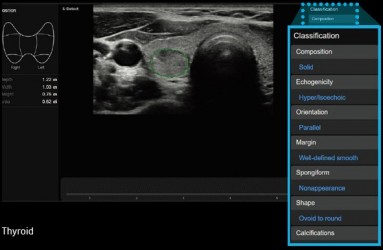

S-Detect™ for ThyroidS-Detect ™ pro vyšetření štítné žlázy využívá pokročilou technologii při odhalování a klasifikaci podezřelých lézí štítné žlázy na základě Thyroid Image Reporting and Data System (TI-RADS) skóre. Tato nejmodernější technologie dovoluje vyšetřit pacienty s jistotou a snadně, poskytuje přesné, konzistentní výsledky včetně funkce automatického reportování. |